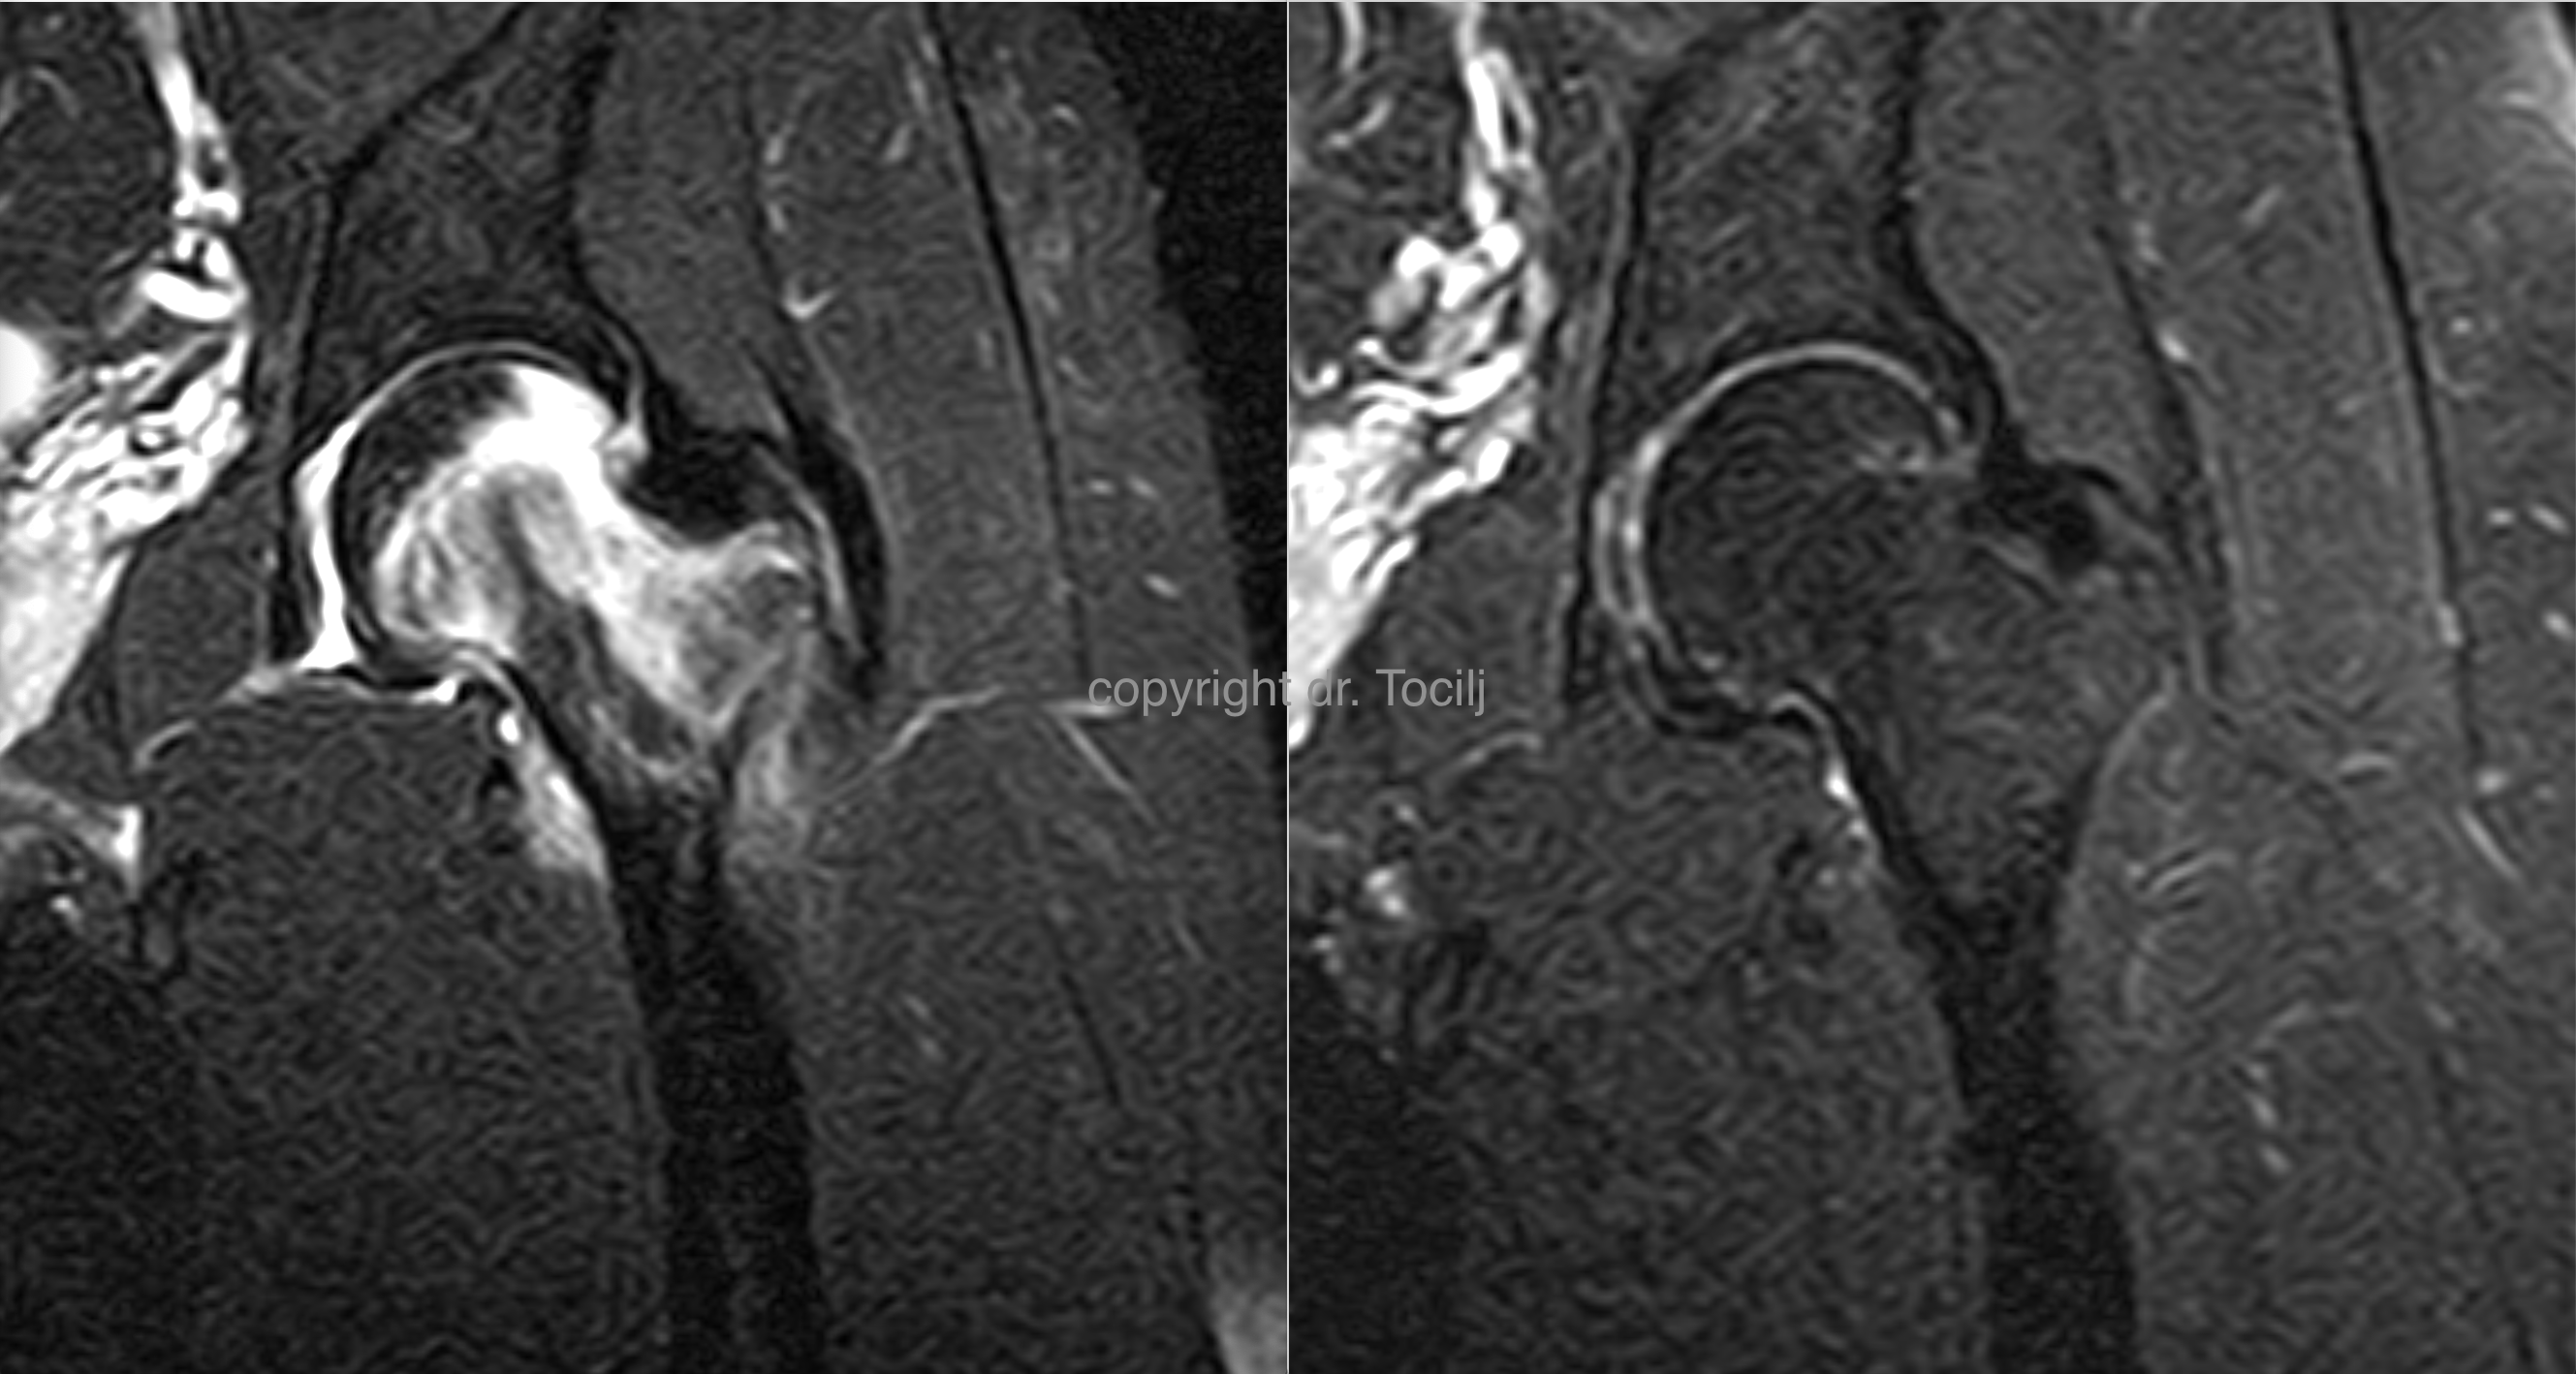

CARTILAGE REGENERATION

Although very complex procedure cartilage regeneration without need for operation can be achieved through combination of i.a. injection, programmed exercise  and physiotherapy without need for long periods of no activity and immobilization.MRI picture before therapy (left) and  after (right).